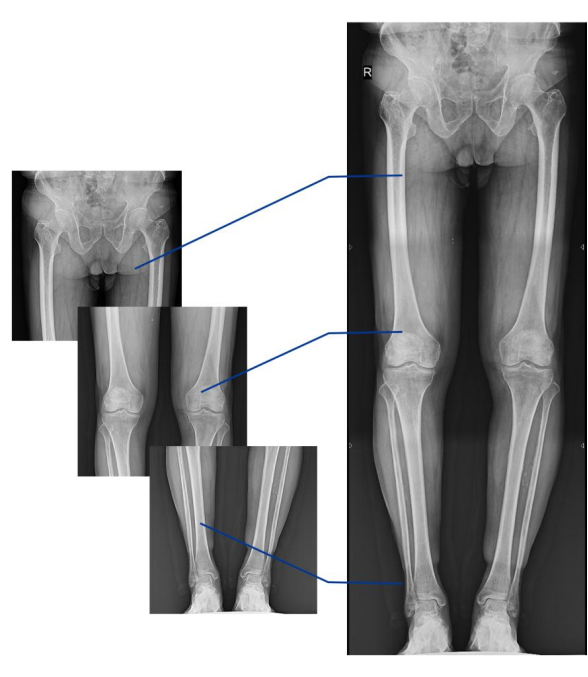

不同于常規(guī)靜態(tài)DR只能進(jìn)行平片攝影檢查,動(dòng)態(tài)DR可以滿(mǎn)足多種臨床檢查需求,包括靜態(tài)檢查、透視檢查、造影檢查、脊柱及下肢全長(zhǎng)拼接檢查,相較于靜態(tài)DR具有豐富的臨床應(yīng)用,且動(dòng)態(tài)DR檢查更精準(zhǔn)、直觀,擺位攝片效率極大地提升,大大節(jié)省拍片時(shí)間。

動(dòng)態(tài)DR影像采集幅面大,17×17英寸超大視野,可覆蓋成年人的全胸全腹,并且能在連續(xù)動(dòng)態(tài)中實(shí)時(shí)高清點(diǎn)片,還可以進(jìn)行視頻保存,在會(huì)診過(guò)程中可以回放影像檢查視頻,從而達(dá)到精準(zhǔn)診斷的目的。同時(shí)動(dòng)態(tài)DR還具有全身拼接功能,尤其適用于全脊柱和全下肢攝影,輔助脊柱畸形矯形治療、康復(fù)檢查,為臨床提供高精度圖像。